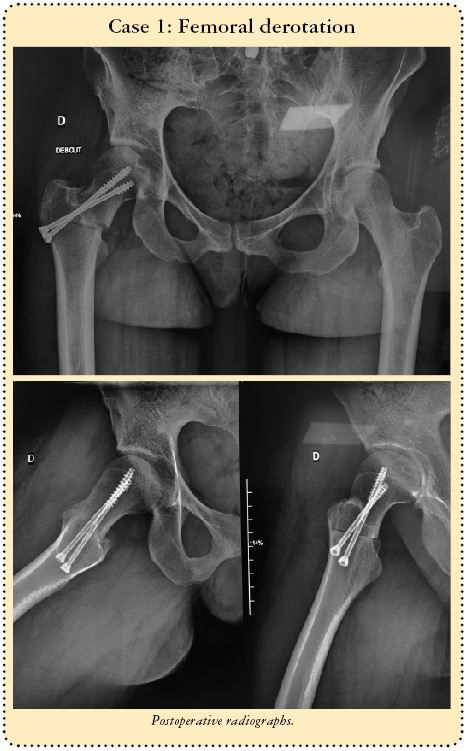

This technique is also very useful for version correction osteotomies at the base of the neck to treat excessive anteversion of the femoral neck. The problem can be corrected at the point of the problem instead of at the femoral diaphysis as when using an intramedullary nail. The need for rotation requires complete mobilisation of the neck, involving a double osteotomy line in order to avoid mobilising the greater trochanter. The first horizontal line terminates at the lower insertion of the greater trochanter on the trochanteric tubercle (Figs 4b and c), with the second line running perpendicular and vertically terminating in the greater trochanter (Fig. 4d) just behind the origin of the femoral neck, leaving the periosteum intact. The line is usually incomplete.

In order to guarantee avoiding the blood vessels when creating this second vertical line, I recommend resection of the anterior cortex only. This will leave a posterior bony hinge to protect the median circumflex vessels.

The foot is placed in sharp medial rotation, then an osteotome is inserted into the vertical line. The foot and knee are then returned to neutral rotation (Fig. 4e). The osteotome holds the neck in medial rotation by opening the derotation osteotomy. The posterior cortex will break naturally and automatically create a posterior hinge.

No tool or instrument should bypass this potentially dangerous region. If the vertical line is sufficiently posterior, there is no great risk since the vessels run in close contact to the femoral neck (Fig 4a). It reaches the neck after passing between the medial and lateral obturator muscles.

Before making the two osteotomy lines, the whole procedure can be made easier by drilling a 3.5mm hole in the anterior cortex anterior to where the two perpendicular lines will join, then using an image intensifier to ensure the optimal positioning of the two osteotomy lines (Fig 4b).

With derotation osteotomies, we always fill open lines using a small allograft fragment (Figs 4f and g).

Nine of the corrections involved a varus-producing osteotomy, five a valgus-producing osteotomy and one femoral derotation for excessive femoral anteversion.